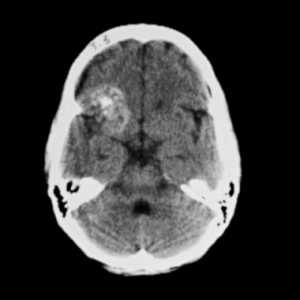

![кавернозная ангиома КТ]()

Кавернозная ангиома правой лобной доли. На компьютерной томограмме без контрастного усиления видно крупное неоднородное образование в лобной доле справа. Образование характеризуется высокой рентгеновской плотностью в своей центральной части и диффузно повышенной плотностью на периферии вследствие наличия в образовании кальцификатов и мелких кровоизлияний.